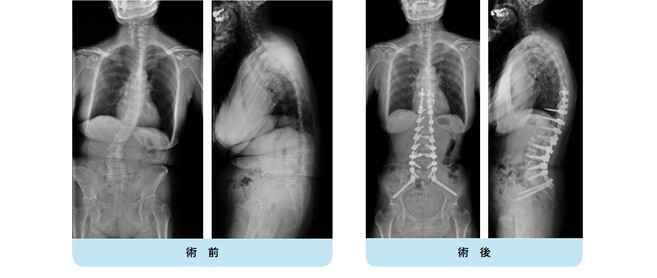

変性後側弯症で正面・側面ともに体幹バランスが破綻しています。

まず腰椎側方進入前方固定術を行い、ある程度の矯正、土台を形成。

1週間後に胸腰仙椎後方矯正固定術を行いました。正面・側面ともにバランスが良好に維持され、難治性の腰痛が改善しました。